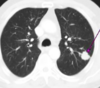

Q

A

Consolidación alveolar

How well did you know this?